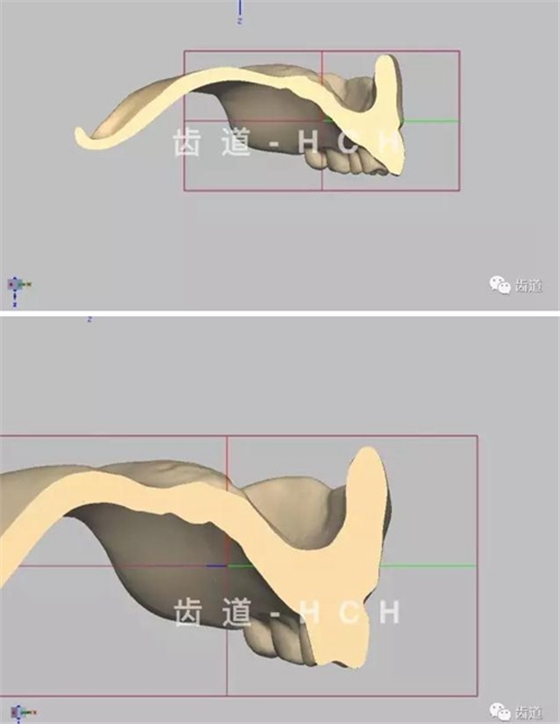

標(biāo)準(zhǔn)全口義齒模型截圖 科貿(mào)嘉友收錄